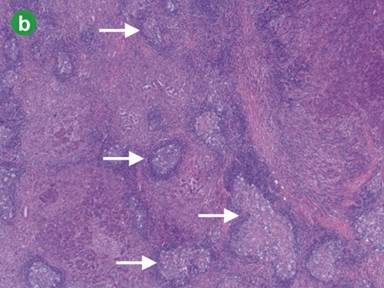

Figure 1. a. Magnetic resonance imaging (MRI) demonstrates two lesions (red arrows: 1.8 cm diameter in uncinate process and 2.3 cm diameter in body of pancreas) which are homogeneously hypo-intensive (T1-weighted sequence). b. Hematoxylin and eosin stained section from the nodule in the body of pancreas reveals an area of nodular lymphoid hyperplasia consisting of several hyperplastic lymphoid follicles with large germinal centers of varying sizes (white arrows) within the pancreatic parenchyma (original magnification x20). c. Higher magnification showing reactive germinal center (gc) with tingible body macrophages with well-preserved mantle zone (mz) and adjacent exocrine pancreatic parenchyma. Pathological diagnosis was pancreatic nodular lymphoid hyperplasia previously called “pseudolymphoma” (hematoxylin and eosin staining; original magnification x100). |

Macroscopic examination of the specimen showed an ill-defined whitish nodule measuring 1.5 cm in diameter in the uncinate and another in the body of the pancreas. The microscopic examination of this area in the body showed nodular lymphoid hyperplasia measuring 1.7x2.0 cm. The lymphoid tissue contained well-formed follicles and large germinal centers with macrophages surrounded by fibrotic stroma (Figure 1bc). The lymphoid follicles were mainly composed of large B cells in the center, with small T-cells at the periphery. A similar focus of nodular lymphoid hyperplasia was identified in the uncinate process measuring 1.5x1.8 cm in size. The tail of the pancreas was unremarkable apart from scattered small foci of lymphoid hyperplasia and a few areas low grade PanIN. Eighteen lymph nodes identified within the specimen were all normal. At this point the probable diagnosis of nodular lymphoid hyperplasia needed to be differentiated from follicular lymphoma (a mature B-cell lymphoma that is thought to originate from cells in the germinal center). Therefore, additional immunostains were performed (Figures 2 and 3). The follicular germinal centers showed CD10(+) and were negative for BCL2. CD21(+) and CD23(+) highlighted dendritic cell meshworks, whereas CD3(+) and CD5(+) showed small T-cells. Cyclin D1 appeared negative in lymphoid cells and kappa/lambda light chain restriction analysis did not reveal a monotypic lymphoid population. Therefore, the appearances confirmed the diagnosis of reactive inflammatory infiltrate and no malignancy. At follow-up, contrast enhanced CT of the chest, abdomen and pelvis 6 months post-operatively has shown no disease recurrence or new lesions.